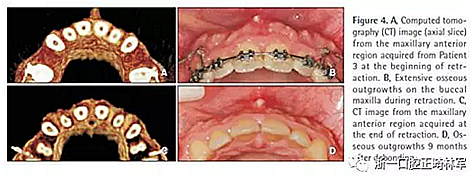

在這名患者觀察到最廣泛和嚴(yán)重的骨增生,且在第一個(gè)月最明顯。拆除托槽9個(gè)月后,這些增生明顯消退但仍舊很明顯(圖4)。內(nèi)收耗時(shí)11個(gè)月。